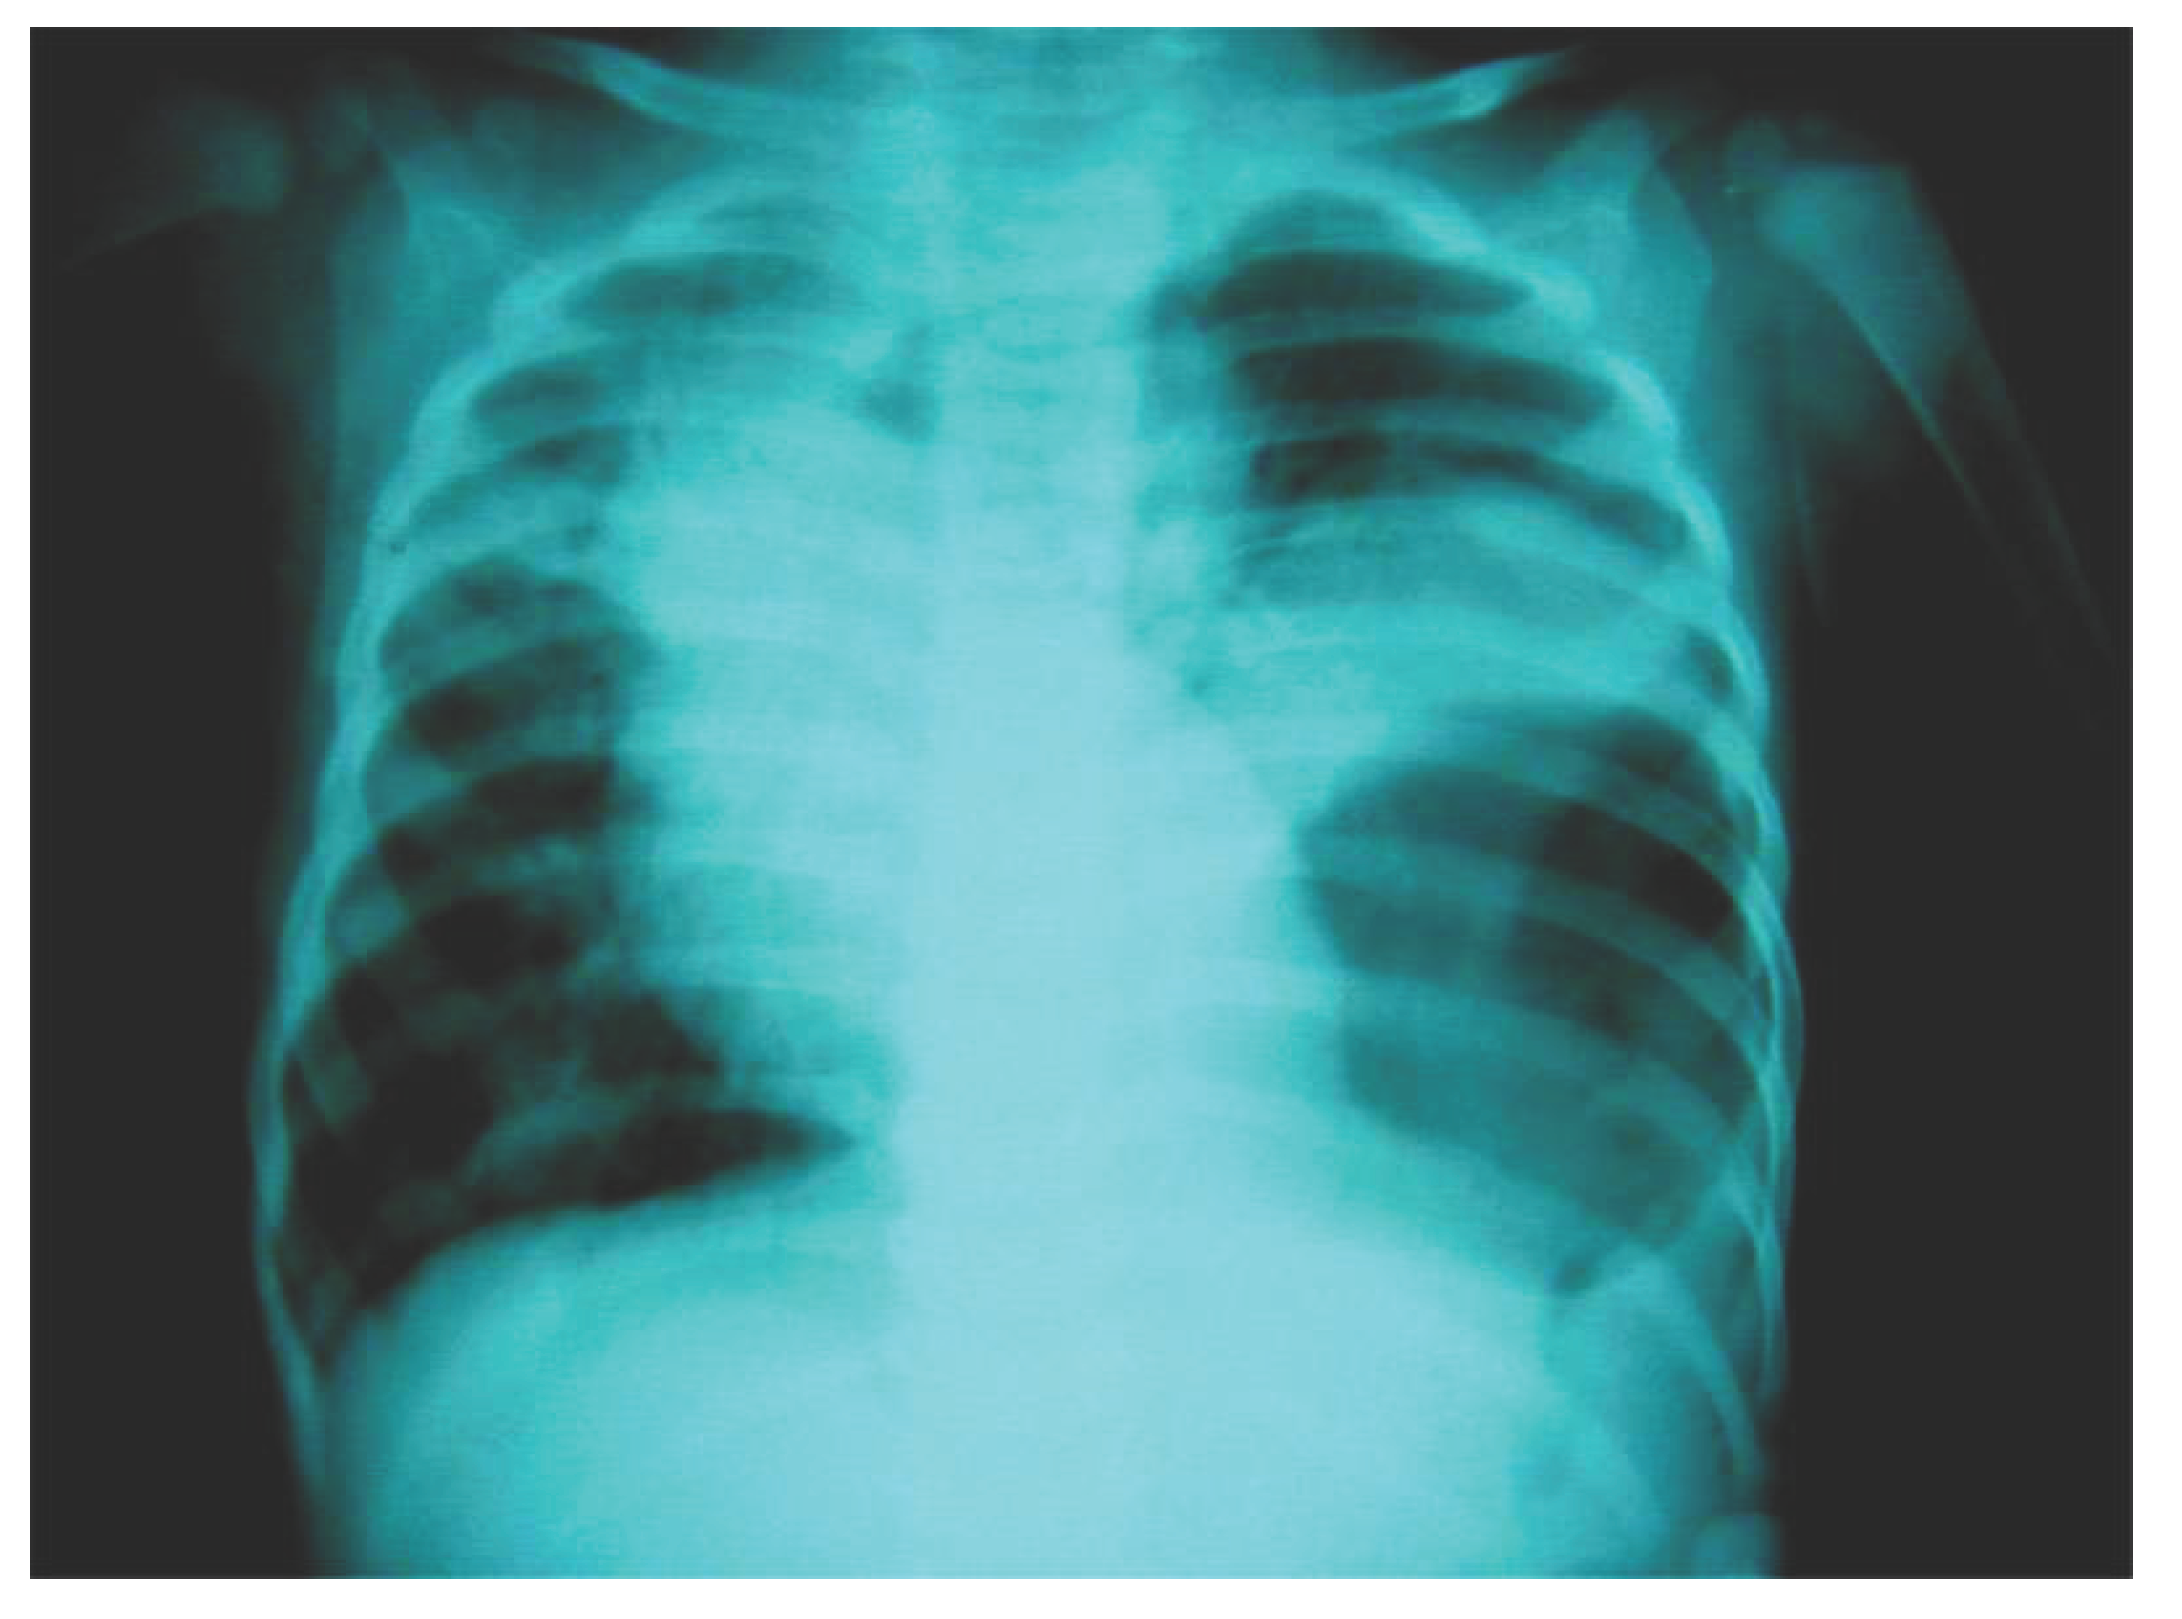

The nasogastric tube decompression was continued. Surgery was delayed, waiting for full recovery from pneumonia. At surgery, a small Bochdalek hernia defect was found containing the stomach and a portion of the splenic flexure of the colon. After reduction of the hernia contents, the posterolateral defect was primarily closed with a patch (Figure 3).

The patient did well postoperatively with resolution of her symptoms and was discharged from the hospital after six days. Follow up after 30 days of surgery revealed marked clinical and radiological improvement.

Figure 3.

Preprints 179744 g003